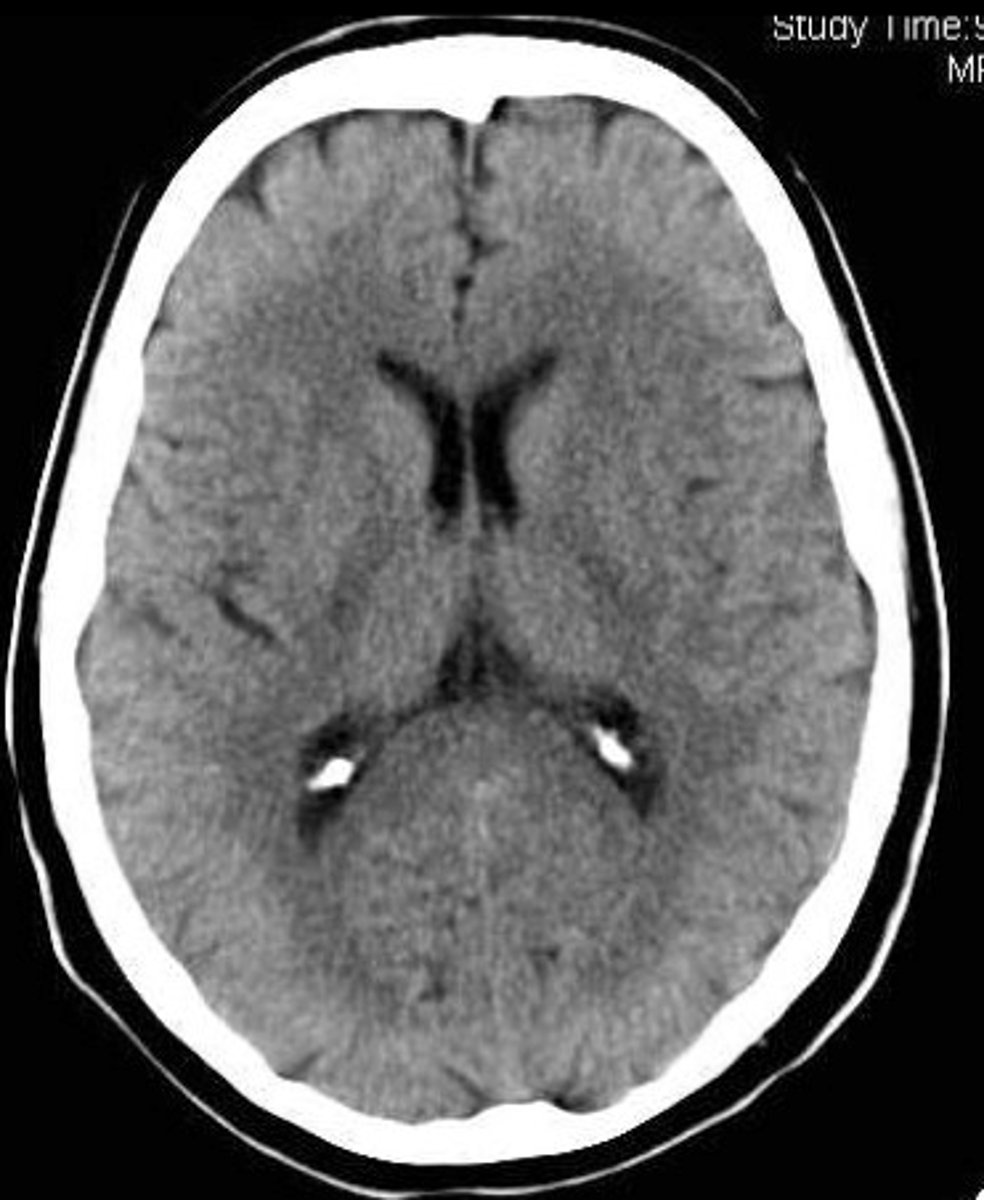

MRI

Magnetic resonance imaging. A technique that uses magnetic fields and radio waves to produce computer-generated images that allows us to see structures within the brain.

uses magnetic fields and radio waves to produce computer-generated images that distinguish among different types of soft tissue (structure)

MRI scan

CT scan

a series of x-ray photographs taken from different angles and combined by computer into a composite representation of a slice through the body.